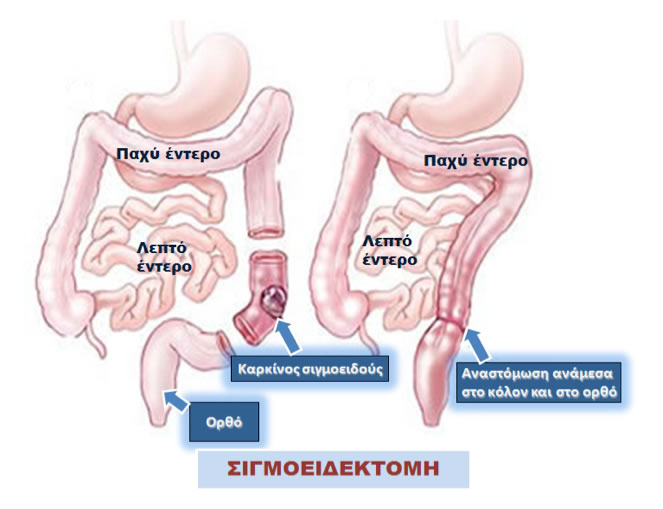

Για πλήρη ίαση, η χειρουργική επέμβαση είναι σχεδόν πάντα απαραίτητη. Κατά τη διάρκεια της χειρουργικής επέμβασης για καρκίνο του παχέος εντέρου, αφαιρείται ο όγκος, λεμφαδένες και μαζί ένα τμήμα του υγιούς/φυσιολογικού κόλου/παχέος εντέρου σε κάθε πλευρά του όγκου. Η δημιουργία κολοστομίας είναι απαραίτητη μόνο σε ένα πολύ μικρό αριθμό ασθενών. Οι εξειδικευμένοι χειρουργοί παχέος εντέρου και πρωκτού έχουν εκπαιδευτεί και γι’ αυτό είναι ικανοί να χρησιμοποιούν ελάχιστα επεμβατικές χειρουργικές τεχνικές, ανάλογα με συγκεκριμένα χαρακτηριστικά του εκάστοτε καρκίνου καλούνται να αντιμετωπίσουν. Ο εξειδικευμένος χειρουργός σας θα συζητήσει αυτά τα χαρακτηριστικά μαζί σας πριν το χειρουργείο. Πρόσθετες θεραπεία με χημειοθεραπεία μπορεί να προσφέρονται μετά τη χειρουργική επέμβαση Ανάλογα με το στάδιο του καρκίνου, είναι πιθανό ο ασθενής να υποβληθεί μετεγχειρητικά σε επιπλέον θεραπεία, δηλαδή σε χημειοθεραπεία . Σε αντίθεση με τον καρκίνο του ορθού, η ακτινοθεραπεία χρησιμοποιείται σπάνια για τον κα

Η χειρουργική αφαίρεση του τμήματος του παχέος εντέρου που έχει προσβληθεί από τον καρκίνο μαζί με τους γειτονικούς λεμφαδένες αποτελεί τη βασική θεραπεία για τον καρκίνο του παχέος εντέρου. Για να επιτευχθεί ίαση η χειρουργική εκτομή είναι σχεδόν πάντα απαραίτητη. Καμία από τις υπάρχουσες θεραπείες με φαρμακευτικά ή άλλα μέσα, όπως με την ακτινοβολία, δεν μπορούν να επιτύχουν τα αποτελέσματα της χειρουργικής θεραπείας. Η χειρουργική θεραπεία, στις περισσότερες περιπτώσεις, θα καταφέρει να διατηρήσει τον ασθενή ελεύθερο νόσου για μεγάλο διάστημα, αποφεύγοντας, ειδικά στους καρκίνους που είναι σταδίου Ι και ΙΙ, την ανάγκη χορήγησης άλλων θεραπειών.

Δύο είναι οι βασικές προσπελάσεις για τη χειρουργική εκτομή του παχέος εντέρου, η οποία όταν αφορά το κόλον λέγεται κολεκτομή:

Όταν ένα τμήμα του κόλου ή του ορθού αφαιρείται, ο χειρουργός συνήθως συνδέει τα υγιή τμήματα του εντέρου που απομένουν. Αυτή η διαδικασία ονομάζεται αναστόμωση. Με τη συνένωση αυτή επιτυγχάνεται η αποκατάσταση της συνέχειας της πεπτικής οδού, έτσι ώστε το περιεχόμενο του εντέρου να προχωρά φυσιολογικά διά του παχέος εντέρου, όπως και πριν από το χειρουργείο.

Τύποι κοινών χειρουργικών επεμβάσεων για καρκίνο του παχέος εντέρου